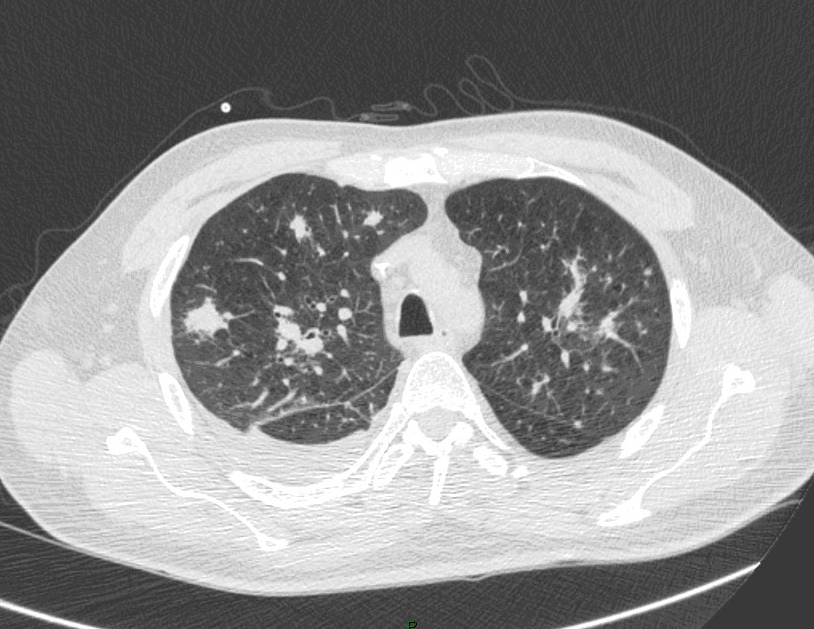

La fièvre persiste malgré les antibiotiques. Cela fait maintenant 5 jours, et vous décidez donc de réaliser un scanner thoracique dont les images sont les suivantes.

Question 13 : Comment décrivez-vous ces images ?

Nodule pulmonaire entouré de verre dépoli

Présence d’un épanchement pleural gauche

Quesyion 14 : Quelle(s) est(sont) alors les hypothèses diagnostiques devant ces images ?

Hypothèse la plus probable devant le terrain de neutropénie prolongée et les images en faveur

Absence de condensations alvéolaire ou de bronchogramme aérien

Aspergillose pulmonaire invasive = infection fongique invasive la plus fréquente chez le patient avec neutropénie prolongée (> 7 jours de neutropénie).

- imagerie :

°précoce : signe du halo : nodule unique ou multiple, avec verre dépoli autour (signe du grelot se voit dans l’aspergillome compliquant une caverne tuberculeuse par exemple) ;

°plus tardif : condensation non spécifique, puis apparition d’un croissant gazeux traduisant la nécrose du parenchyme.